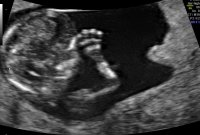

Lille trille vokser videre ❤️ 11+0 i dag, ble målt til 11+2.

Nakkefold er på 1mm, normalgrensen var visst opp til 3,5mm. Sjekket papirene fra sist, og der hadde engel 4mm..

Alt ser bra ut til nå, og utifra hva ultralydjordmor sa, så er alt perfekt denne gangen ❤️ Neste uke blir det mer anatomisk gjennomgang, for da er jeg over i uke 12, men min største milepæl blir å nå 15uker :)